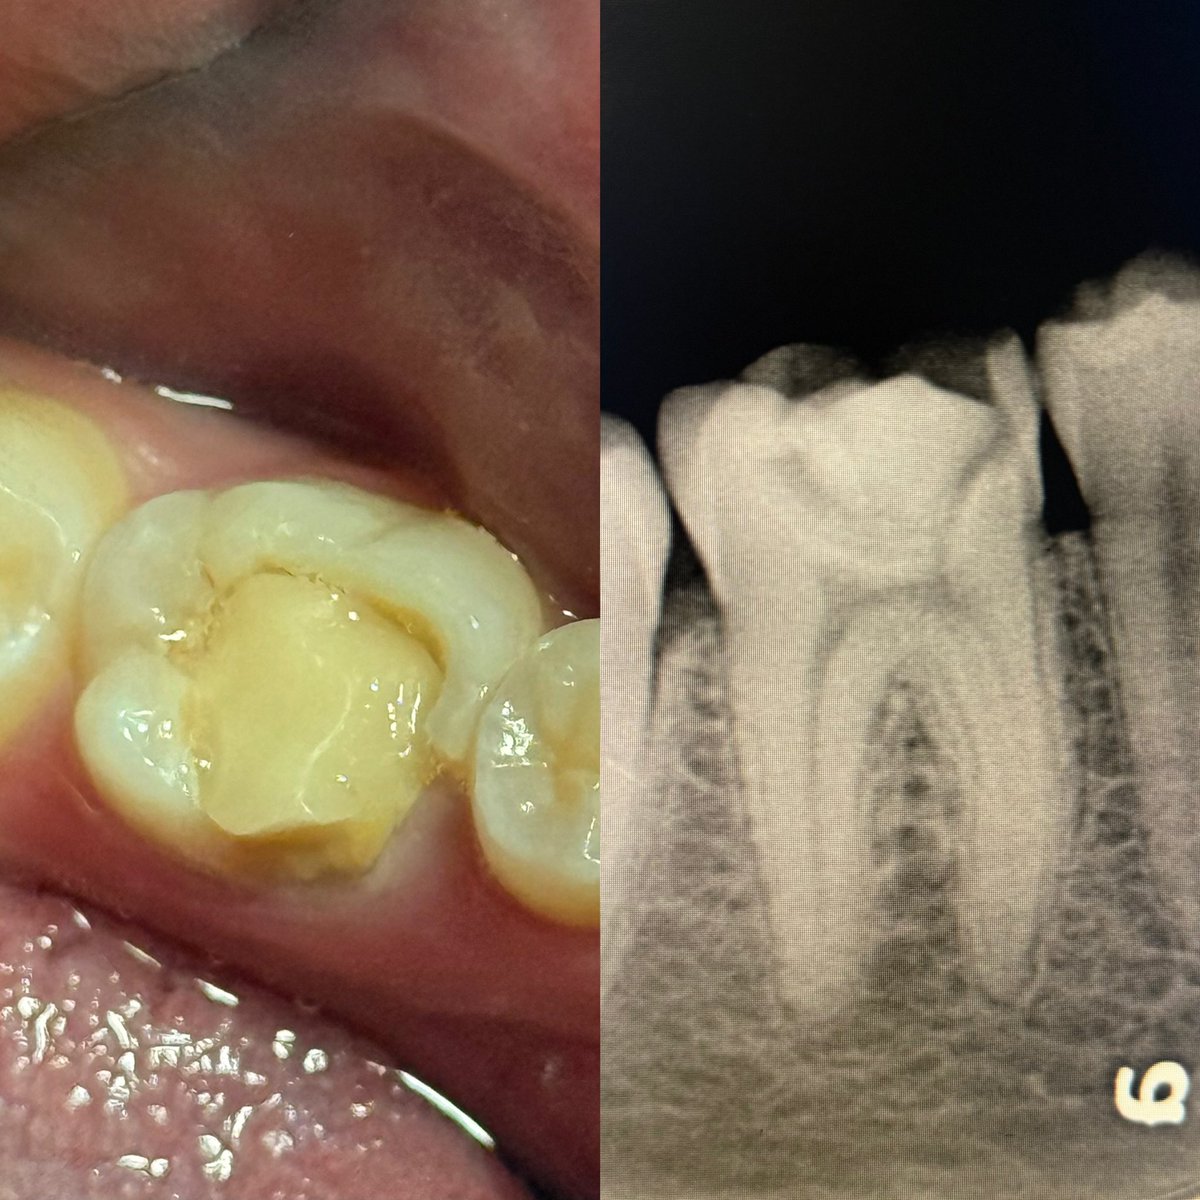

حالة جديدة اليوم ❤️

Root Canal Treatment for #36

The patient complained of severe pain,after examination we decided to do RCT.

Dx: SIP,NAP

ML wall is replaced then started RCT.

Single Cone and BC Sealer are used

✅✅

#endodontics